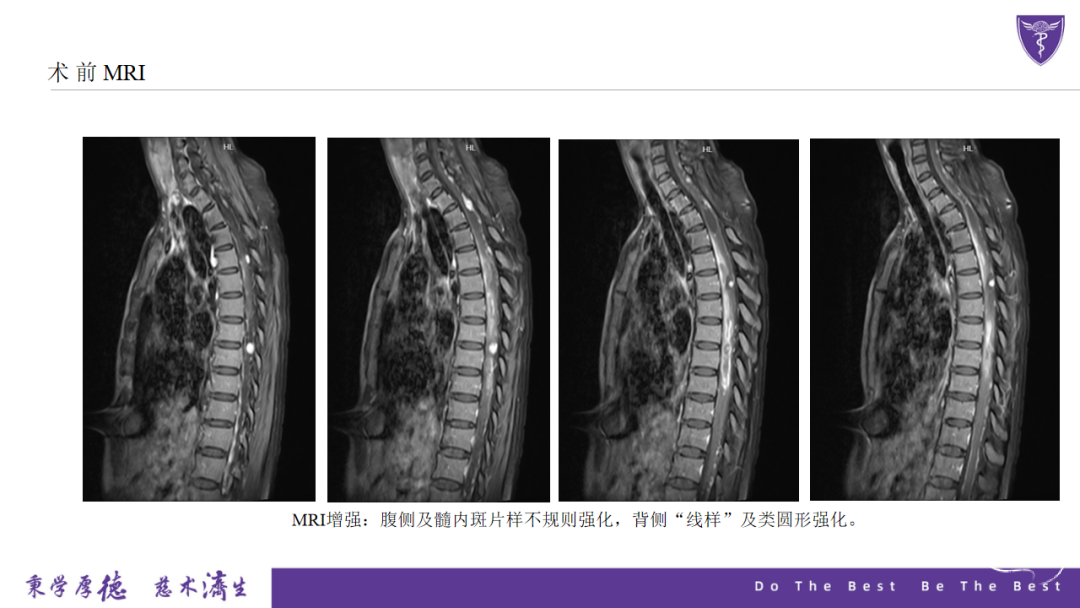

术前